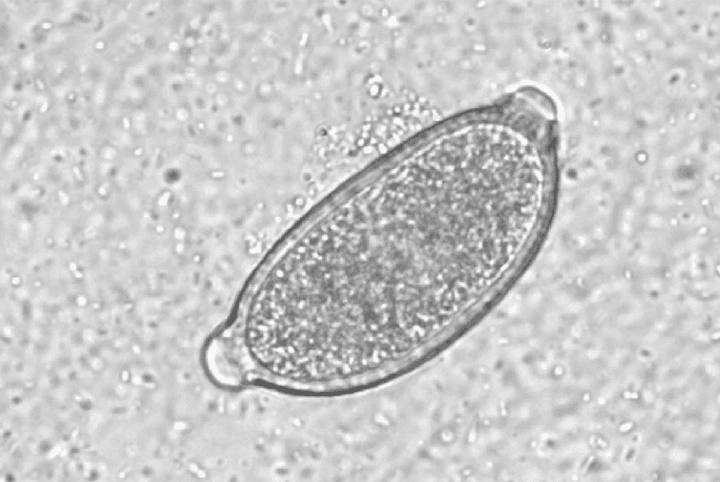

اندازه تخم‌ها ۲۱*۴۵ میکرون و مشابه تخم‌های تریکوسفال است. اما دو انتهای قطبی آن کمتر برجسته به نظر می‌رسد و پوسته‌ی مخطط ضخیمی دارد.